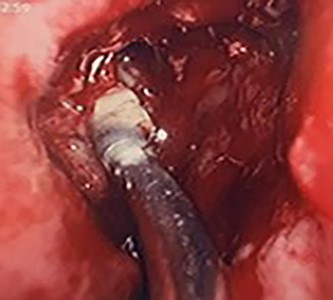

Flexible nasendoscopy offered little in terms of diagnostic benefit. An exam under anesthetic with a view to removing the ectopic tooth via endoscopic sinus surgery was warranted. Right middle turbinate trimming along with a right maxillary antrostomy was performed. The tooth was immediately identified at the antrum as depicted in Figs 4–6. The bony capsule of the tooth was entered and, on manipulation, a second ectopic tooth was identified (Fig. 7) both of which were removed en bloc. The cystic component within the maxillary sinus was marsupilized and extracted. The sinus cavity can be viewed with the utilization of 70° endoscope (Fig. 8). This facilitated bipolar cautery of the base of the cyst and confirmed the absence of an oroantral fistula.

Intra-operative image of the ectopic tooth at the right osteomeatal complex, with curved suction facilitating enucleation.